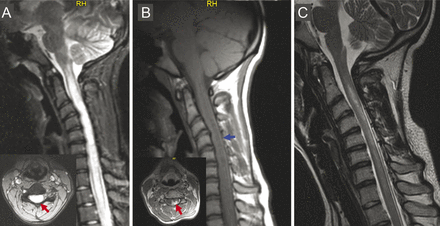

一个17岁的女孩出现急性发作时颈椎疼痛,其次是左臂的弱点和步态障碍。脊髓星形细胞瘤诊断的磁共振成像表现在门诊设施(图中,A和B)。病人被送进神经外科部门接受脊髓切片。第二个神经评估表示视neuromyelitis(动),最可能的诊断,这证实了NMO-immunoglobulin G血清阳性。该患者使用血浆置换联合救援与大量的临床和放射(图中,C)改进。

动与纵向呈现广泛的脊髓病变导致“肿绳”外观和涉及整个横截面积的绳可能最初误诊为脊髓髓内肿瘤。1,2脊髓肿瘤的鉴别诊断应该添加动包括横向脊髓炎、脊髓缺血,系统性自身免疫性疾病。

(A)矢状T2 fat-saturation颈绳MRI显示了一个广泛的(C2-T4级别)hyperintense病变包括几乎整个线截面(插入、红色箭头)。(B)矢状T1显示“肿绳”外观与中部地区hypointensity(蓝色箭头),可能反映了坏死,坏死被发现在患者的病理标本neuromyelitis视。增强在左侧横截面脊髓的钆注射后(插入、红色箭头)。(C)实质性决议T2-hyperintense病变的显示在后续救援血浆置换后矢状脑磁共振T2。